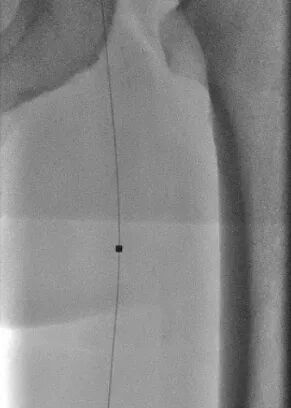

另一个病例中,患者病情更为复杂。术前CTA检查显示,其股浅动脉至腘动脉全程闭塞,血管外科将这种情形称为“长段无光区”。传统治疗中,开通此类如同“水泥管”般的长段闭塞血管,难度极大,术者如同在黑暗中摸索,导丝极易误入内膜下形成夹层,导致手术失败。

2.png

术中,血管外科团队以IVUS为“导航”,在其实时监视下,导丝精准找到血管真腔入口,顺利通过全程闭塞段,成功避免夹层发生,顺利打通患者腿部“生命通道”。针对血管开通后管腔内的严重增生性病变,团队采用准分子激光消融术进行减容处理,通过激光导管冷光源精准气化斑块,进一步恢复了血管正常内径。

经“精准诊断+精准操作”的一体化治疗,手术取得圆满成功。患者术前因严重缺血无法测出踝肱指数(ABI),术后ABI值恢复至0.92并接近正常水平,同时静息痛完全消失,重新恢复了自主行走能力,生活质量得到根本性改善。